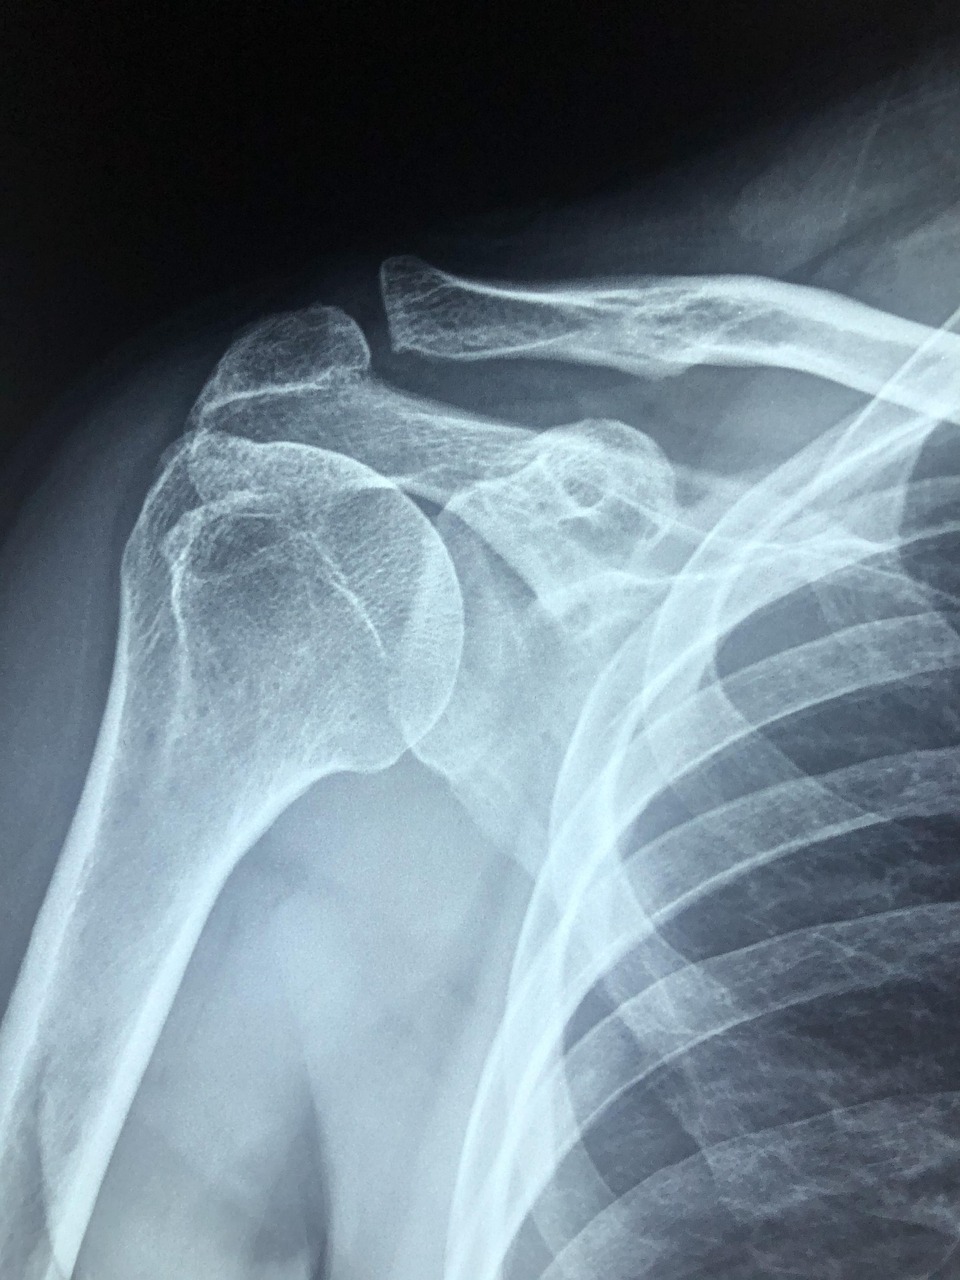

폐경은 여성에게 단순히 생리가 멈추는 생물학적 현상이 아닙니다. 뼈, 혈관, 뇌를 보호하던 여성호르몬(에스트로겐)의 보호막이 사라지는 중대한 전환점이죠. 미국 노년학회에 따르면, 폐경 후 여성은 남성에 비해 골다공증성 골절 위험이 3배 이상 높고, 심혈관 질환 발병률도 급격히 증가한다고 합니다. [출처: The Gerontological Society of America] 저는 이 사실을 알고 나서 막연한 두려움 대신, '지금부터라도 제대로 준비하면 건강한 노년을 맞이할 수 있다'는 희망을 가지게 되었어요. 그리고 의사 선생님의 조언을 바탕으로 질병 예방을 위한 저만의 장기적인 건강 계획을 세웠답니다.

뼈는 우리 몸의 기둥이자, 칼슘을 저장하는 중요한 기관입니다. 그런데 폐경 후 에스트로겐 감소로 뼈를 만드는 조골세포의 기능이 약해지면서 뼈 밀도가 급격히 낮아져요.